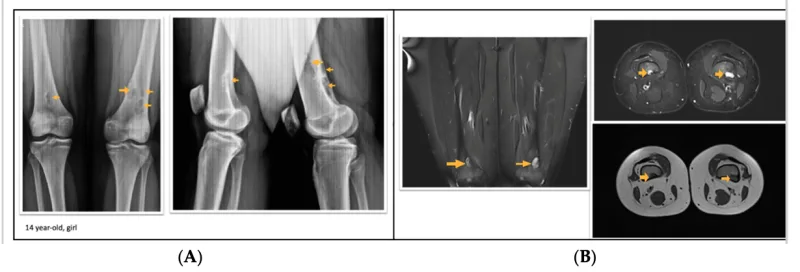

X線写真では, 大腿骨に孔が開いたように丸く透けて見える病変が認められます.

MRIでは, 病変に一致して, 変化が認められます.

大腿骨の骨腫瘍が疑われる小学生が, 紹介で受診されました.

X線写真では, 大腿骨遠位部に孔が開いたような円形の透亮像を認め, MRIでも同部位に一致した信号変化を確認.

画像所見から, 『骨幹端線維性欠損(非骨化性線維腫)』と診断しました.

症状はなく. 成長とともに自然消失する良性の腫瘍類似疾患であることを説明し, 治療は不要としました.